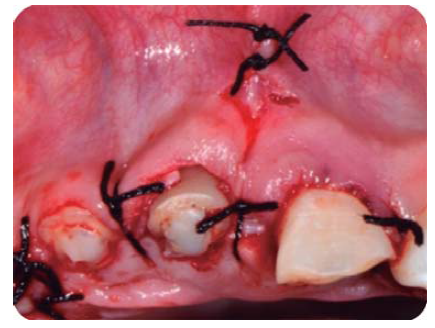

Con una hoja de bisturí 15c, se realiza una incisión a bisel interno y luego una intrasurcal para eliminar un collar de encía y continuar levantando un colgajo de espesor total para exponer la estructura radicular remanente (Figura 8).

Se realizan las medidas con una sonda periodontal, para determinar la cantidad de tejido óseo que se debe eliminar con la osteotomía y osteoplastia para asegurar el efecto férula necesario para las restauraciones provisionales. Se mide con la sonda para asegurar una osteotomía de mínimo 3 mm (Figura 9), se procede a suturar con puntos simples (Figura 10).14

En la historia clínica, el paciente reveló que sus dientes incisivos centrales superiores presentaban diastemas, por lo cual durante la misma cirugía se procede a liberar el frenillo labial superior por medio de una frenilectomía, ya que su inserción era baja (Figura 10).15